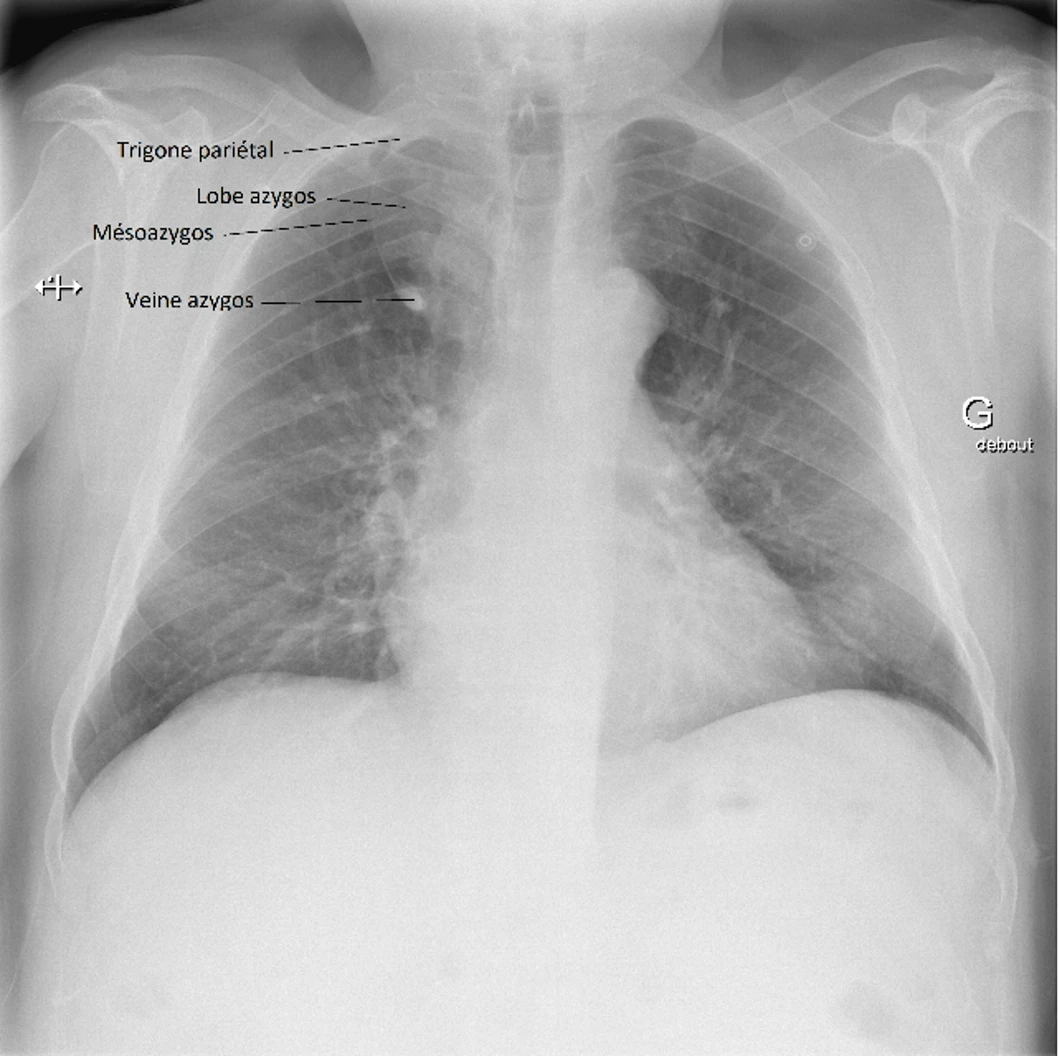

Les signes radiologiques classiques sont :

1. Au niveau paratrachéal droit :

• Une image de larme par la présence de la veine azygos déplacée latéralement et se retrouvant piégée dans le parenchyme pulmonaire et les plis de la plèvre

• Une image de virgule inversée par la veine qui indente le lobe supérieur droit et crée une scissure accessoire (pli de la plèvre pariétale et viscérale, mésoazygos)

2. À la portion supérieure de la fissure : une opacité triangulaire, le trigone pariétal, qui est du tissu extrapulmonaire pris en sandwich lors de la migration de la veine azygos.

3. Au bord inférieur de la bande paratrachéale droite : le renflement habituellement présent en raison du passage de la veine azygos à l’angle trachéobronchique n’est pas visible.